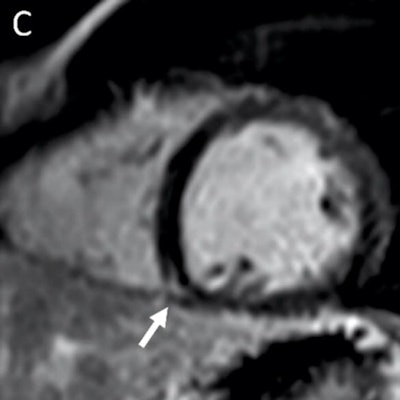

The researchers found that 37 athletes were diagnosed with COVID-19 myocarditis, which showed on MRI as late gadolinium enhancement. Out of these, nine (24%) had clinical myocarditis and 28 (76%) had subclinical myocarditis.

Follow-up cardiac MRI testing was performed in 27 athletes. Imaging showed that T2 elevation in MRI resolved in all patients and late gadolinium enhancement was found in 11.